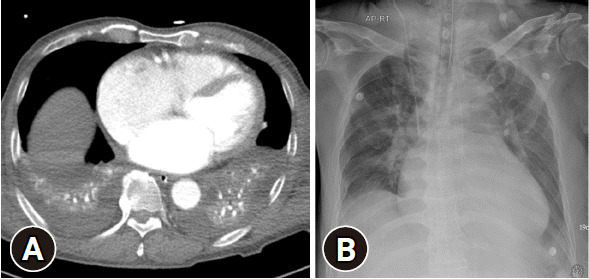

误解放射检查结果可能导致不必要的干预和潜在的患者伤害。在危急情况下,应对健康受损的创伤患者所需的紧迫性可能会增加误读胸部 X 光片的可能性。我们介绍了一名创伤患者的病例报告,该患者在复查胸部 X 光片时将皮肤褶皱伪影误认为是气胸,结果导致不必要的胸管插入。我们希望通过考虑位置、形状、锐利度和血管标记等因素,帮助其他人区分外伤患者胸部 X 光片上的皮肤皱褶和气胸。

Misinterpreting radiographic findings can lead to unnecessary interventions and potential patient harm. The urgency required when responding to the compromised health of trauma patients can increase the likelihood of misinterpreting chest x-rays in critical situations. We present the case report of a trauma patient whose skin fold artifacts were mistaken for pneumothorax on a follow-up chest x-ray, resulting in unnecessary chest tube insertion. We hope to help others differentiate between skin folds and pneumothorax on the chest x-rays of trauma patients by considering factors such as location, shape, sharpness, and vascular markings.